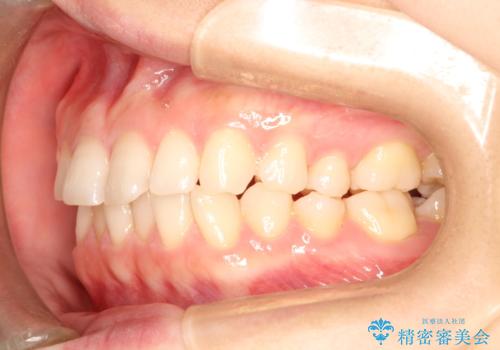

- 前歯のガタガタを綺麗にしたいとのことでインビザラインにて治療を行いました。

治療前は臼歯部反対咬合のため下顎が偏移し正中がずれていましたが、臼歯部反対咬合を改善したことで、正中のズレを改善することができました。